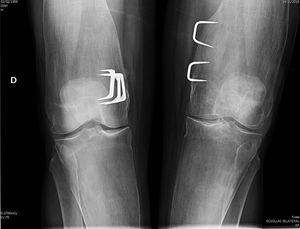

Clinical observationWe present the case of a 58 year old man who was sent to the outpatient rheumatology department on suspicion of bone fragility. At 6 years of age he had undergone surgery for marked bilateral genu valgum and at the time there was a suspicion of congenital osteopathy. The operation improved the statics of his lower limbs and the patient was able to have a normal life, with no relevant pathologies until 57 years of age, when, after a low intensity trauma, he suffered a fracture to the left collarbone and acetabulum. In the medical file no risk factors of osteoporosis or family history or personal history of interest were recorded, except for the before-mentioned surgical intervention. Physical examination revealed an adult with a good general appearance, with no craniofacial deformities, a moderate bilateral genu valgum and the limitations of the recent fractures, for which surgery was required. He was 182cm tall, weighed 81kg (BMI 24.45kg/m2), with nothing remarkable in the rest of the physical examination. General analyses tested normal, with ionic serum calcium of 2.41mmol/l, total alkaline phosphatase of 115u/l, and 25-OH-D3 of 32.8ng/ml and PTHi of 56pg/ml. Bone densiometry showed a T-score of −1.4 SD in lumbar spine (928mg/cm2) and −2.2 SD in neck of the femur (625mg/cm2). A radiographic study revealed a pattern which is characteristic of PD, with a metaphyseal enlargement of the tubular bones (Fig. 1), marked cortical thinning and normal epiphyseal morphology.

DiscussionOur patient met with the radiographic characteristics of PD in the adult, which include a metaphyseal expansion of the long bones and a marked cortical thinning.8,9 All the long bones may be affected, although the characteristic findings are most obvious in the proximal tibia and in the distal femur (with the typical appearance of the “Erlenmeyer flask”) The craniofacial bones may be affected by discreet and occasional changes, such as patched osteosclerosis and obliteration of paranasal passages. However, when these alternations are marked they should rule out other hereditary disease, especially craniometaphyseal dysplasia, which shares with PD abnormal metaphyseal modelling, but which is clearly differentiated because the affected patients present a very unusual facial features, with hypertelorism and thickening of the nasal bridge, and there is no involvement of collarbone, ribs and ischium pubis branches. Camurati–Engelmann disease is also included in the group of metaphyseal dysplasia's but, unlike Pyle's disease, it causes hyperostosis at the skull base and cortical thickening in the long bones. Other processes to consider in the differential diagnosis of PD are osteopetrosis, where apart from the increase in bone density which characterises the group, images of “bone within bone” are appreciated, both in the vertebral bodies and in the diaphyseal and metaphyseal regions of the tubular bones. Other diseases to take into account in the differential diagnosis are Guacher's disease, Niemann–Pick's disease and the Thalassemias disorders, although these are easily ruled out by the medical file and additional tests, and also by the absence of extraosseous compromise and normal lab test results observed in Pyle's disease.